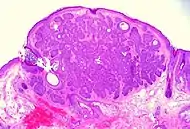

| Cystic basal-cell carcinoma | Morphologically characterized by dome-shaped, blue-gray cystic nodules.[2] | ![]() | |